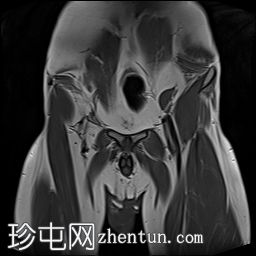

MRI

左侧阴囊空虚。

左侧睾丸位于盆腔左侧前壁,腹股沟管上方。其体积较小(与对侧正常的右侧睾丸相比)。T2加权像呈高信号,T1加权像呈低信号,未见明显局灶

性病

变。

右侧睾丸位于右侧阴囊内,大小和形状正常。